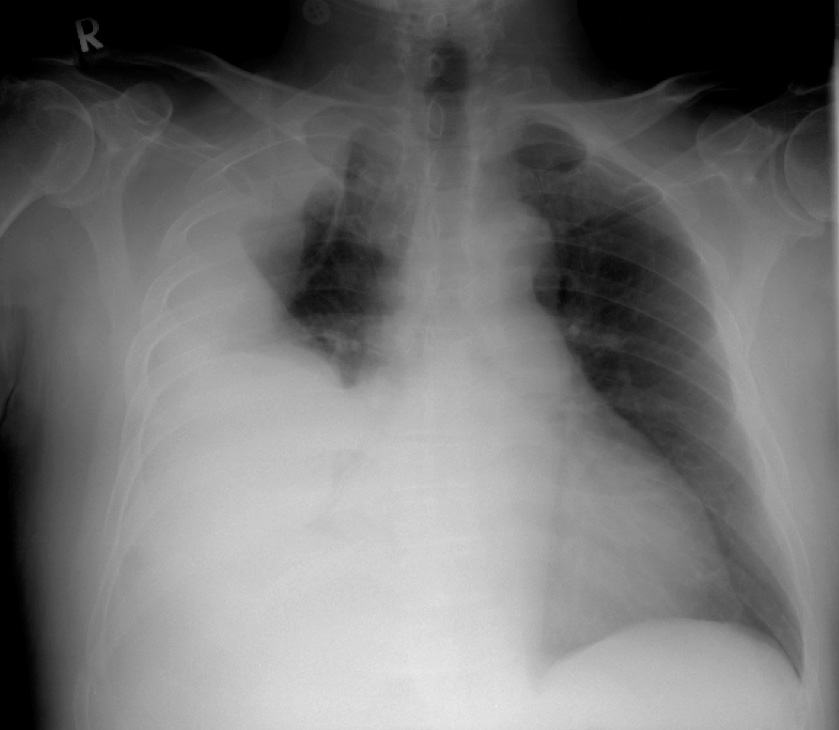

The chest X-ray and subsequent representative CT thorax images are given below, showing a massive right-sided pleural effusion that is also multi-loculated..